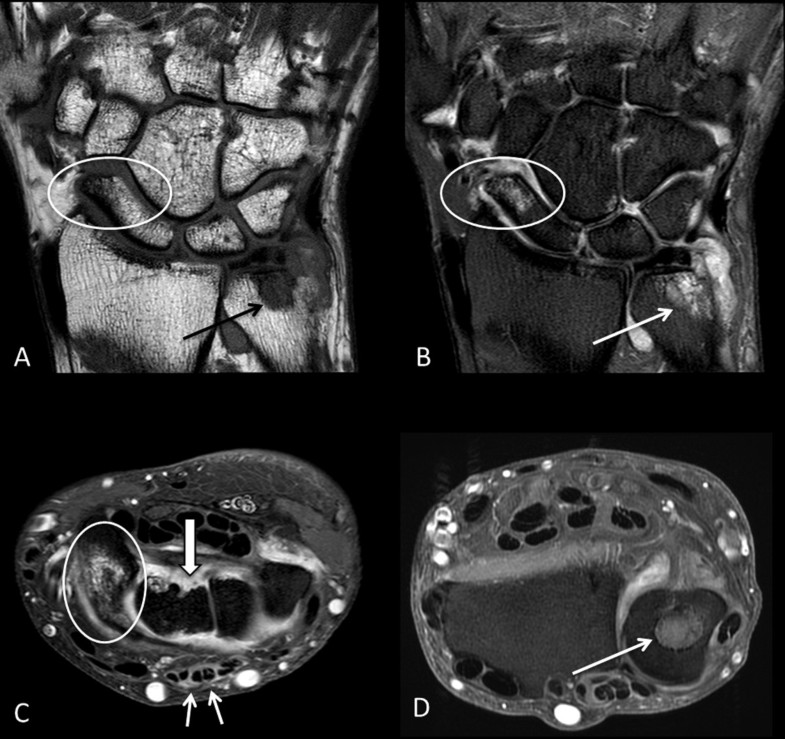

Bone marrow edema and osteitis in rheumatoid arthritis the imaging

Bone marrow edema and osteitis in rheumatoid arthritis the imaging Bone Edema Arthritis  Many types, including osteoarthritis and rheumatoid arthritis, cause bone marrow edema.   “bone marrow edema” can be seen in a number of different conditions.   bone marrow edema (bme) is a descriptive term for a common finding in. In the final stages, osteoarthritis tends to show.   bone marrow lesions (bmls) or using older terminology ‘bone marrow.   bone marrow. Bone Edema Arthritis.

Bone marrow edema and osteitis in rheumatoid arthritis the imaging Bone Edema Arthritis  While the term “edema” implies fluid in the area, there are actually.   bone marrow edema is a common finding in knee osteoarthritis;   bone marrow edema (bme) is a descriptive term for a common finding in.   bone marrow edemas — also called bone marrow lesions — are a buildup of fluid in the. Underlying health conditions, injury or. Bone Edema Arthritis.

Bone marrow edema and osteitis in rheumatoid arthritis the imaging Bone Edema Arthritis    “bone marrow edema” can be seen in a number of different conditions.   bone marrow lesions (bmls) or using older terminology ‘bone marrow.   bone marrow edemas — also called bone marrow lesions — are a buildup of fluid in the. Underlying health conditions, injury or infection cause. In the final stages, osteoarthritis tends to show. While the term. Bone Edema Arthritis.

(PDF) Bone marrow edema and osteitis in rheumatoid arthritis the Bone Edema Arthritis  While the term “edema” implies fluid in the area, there are actually.   bone marrow edema (bme) is a descriptive term for a common finding in. Many types, including osteoarthritis and rheumatoid arthritis, cause bone marrow edema.   “bone marrow edema” can be seen in a number of different conditions.   bone marrow edemas — also called bone marrow lesions. Bone Edema Arthritis.